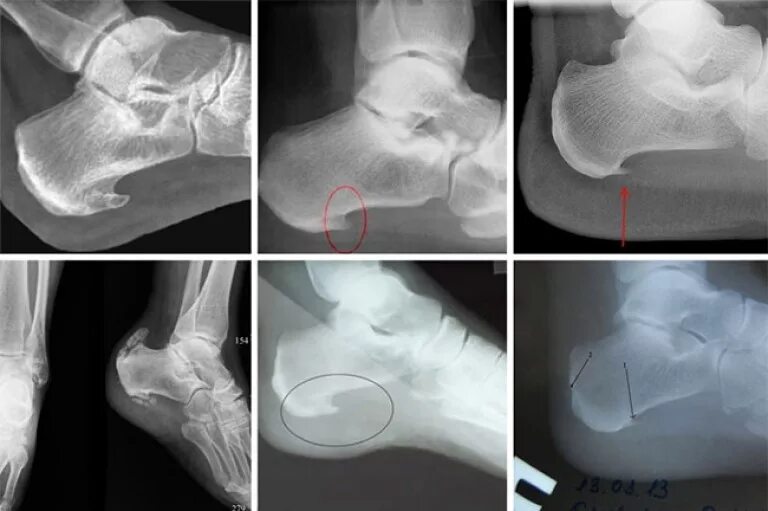

Синдром шпора пяточная